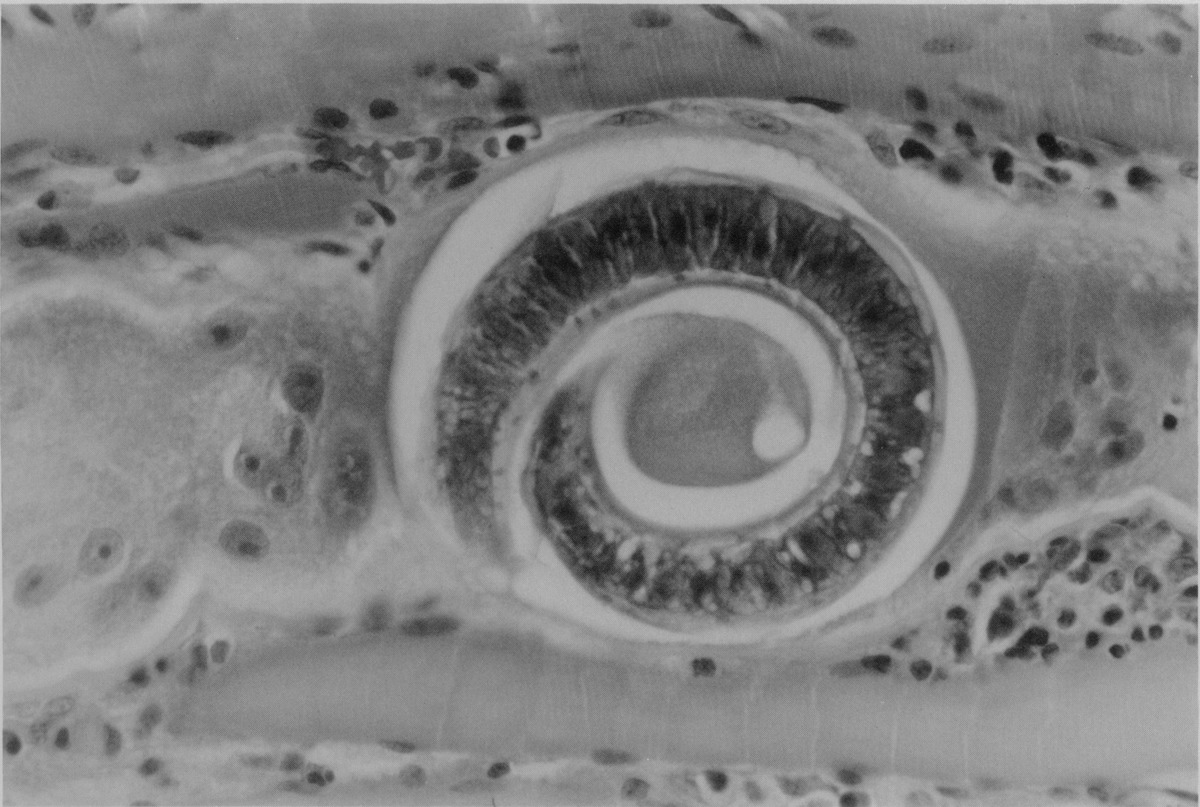

ANSWERS: A=3, Sickle cell disease; B=1, Giardia lambia;, C=4, Trichinosis;